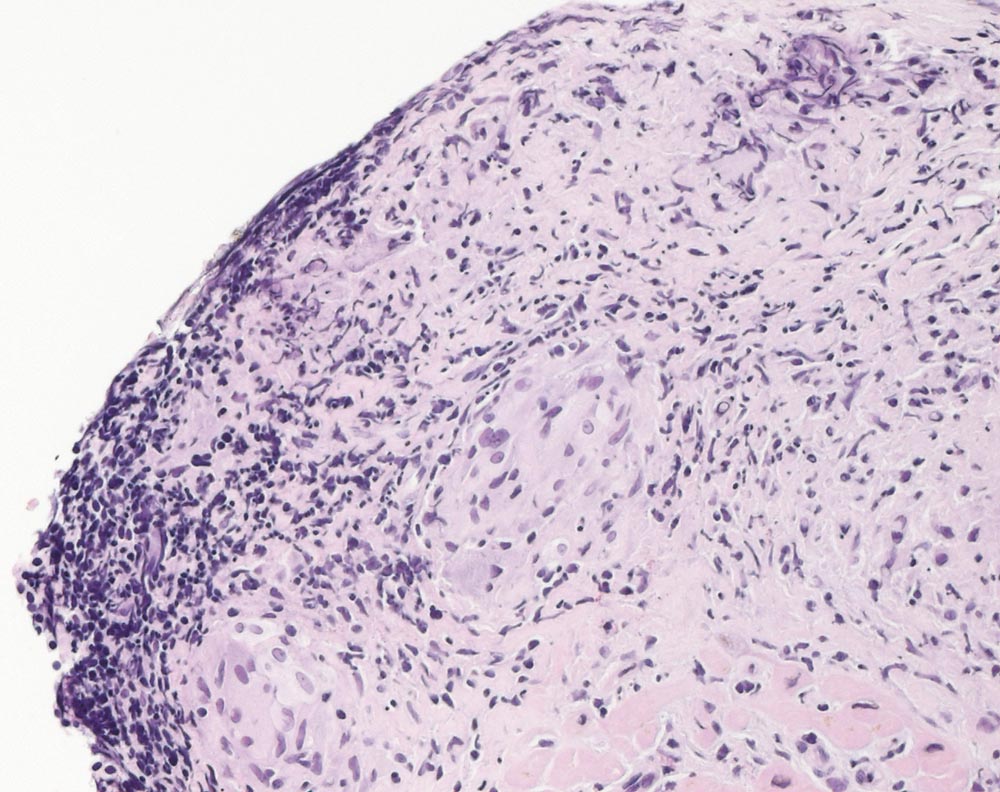

Sarkoidose des Myokards

Systemerkrankung/Immunpathologie

Herz rechts

Kardiovaskuläres System

Endokardiale fibrosierte epitheloidzellige Granulome.

AV-Block. Late enhancement in der MRI Untersuchung septal. Keine extrakardiale Sarkoidosemanifestationen. DD Sarkoidose, Myokarditis, andere chronisch entzündliche Erkrankung des Myokards.

Histologie

200